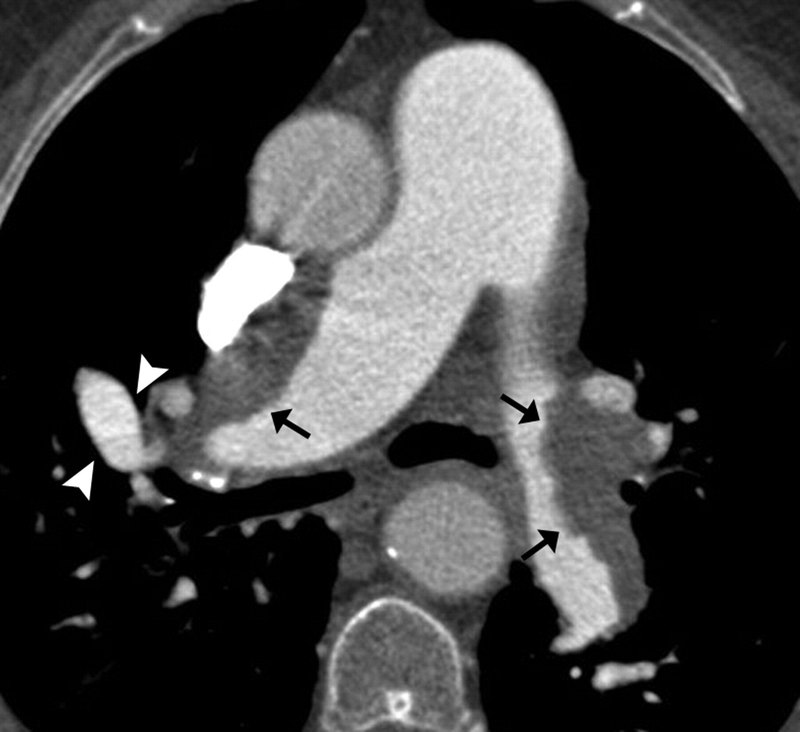

CTEPH的病因:為何血栓會引發(fā)肺動脈高壓?1.初始誘因:肺動脈血栓栓塞急性肺栓塞未完全溶解部分患者發(fā)生急性肺栓塞后,血栓未被身體完全溶解或吸收,殘留的血栓堵塞肺動脈分支(如圖1黑色箭頭所指)。??正常情況:人體通過纖溶系統(tǒng)逐漸溶解血栓,血管再通。??CTEPH情況:血栓機化(變硬)、黏附在血管壁上,形成“瘢痕樣”阻塞。2.血管重塑:肺動脈高壓的關(guān)鍵機制殘留血栓會觸發(fā)血管壁的異常修復反應,導致:血管狹窄:血栓機化后壓迫血管腔。小血管病變:下游未堵塞的小肺動脈因血流減少而收縮、內(nèi)膜增厚(如圖2)。血流阻力增加↑:肺動脈網(wǎng)絡變窄或堵塞,右心室需更用力泵血,最終導致肺動脈壓力升高。3.危險因素以下情況更易發(fā)展為CTEPH:反復肺栓塞病史凝血功能異常(如抗磷脂抗體綜合征)脾臟切除術(shù)后慢性炎癥性疾病不明原因的肺栓塞發(fā)病時間至診斷時間超過2周的肺栓塞